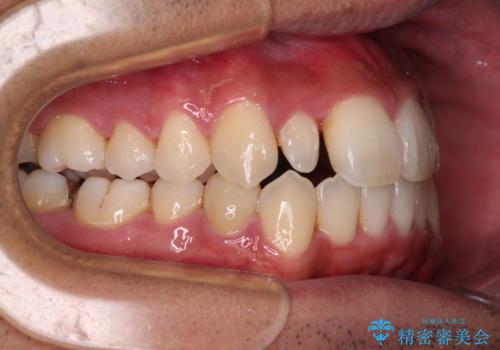

- 前歯のデコボコとクロスバイトを気にして来院された患者様です。

下顎の歯列弓に対して上顎歯列弓がやや小さく、側方の歯を中心にクロスバイトが見受けられました。

クロスバイトの改善は、インビザラインの場合歯髄壊死のリスクや咬み合わせが改善しきらないリスクがあるため、ワイヤー矯正をお勧めすることが多いですが、患者様の希望によりインビザラインにて矯正治療を行うこととしました。